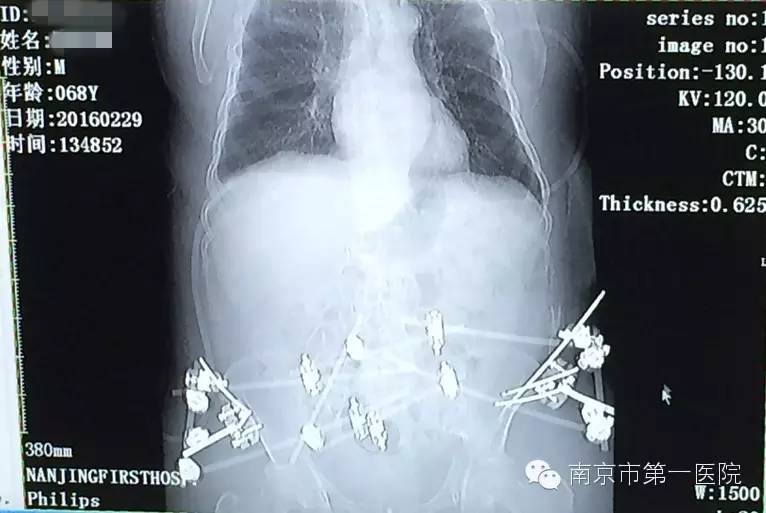

1月25日,由于车祸造成老张骨盆内有血管损伤,在他病情相对稳定后,医生准备对其造影介入手术,安置防血栓滤网,防止肺血栓再次发生。手术过程中,他又出现21日的症状,心肺复苏抢救10分钟后,终于再次将他从死亡线上拉了回来。

“老张盆骨的血管有损伤,血管壁就会很毛糙,失血性休克会导致血液流动速度缓慢,容易形成血栓,这也是老张出现危险的主要原因。心肺复苏后,随后对他进行了血栓滤网的放置,后来再也没有出现类似情况了。”郑曙云还表示,经过一系列的抢救治疗,老张已经脱离危险,情况良好,以后还能像正常人一样自理生活。